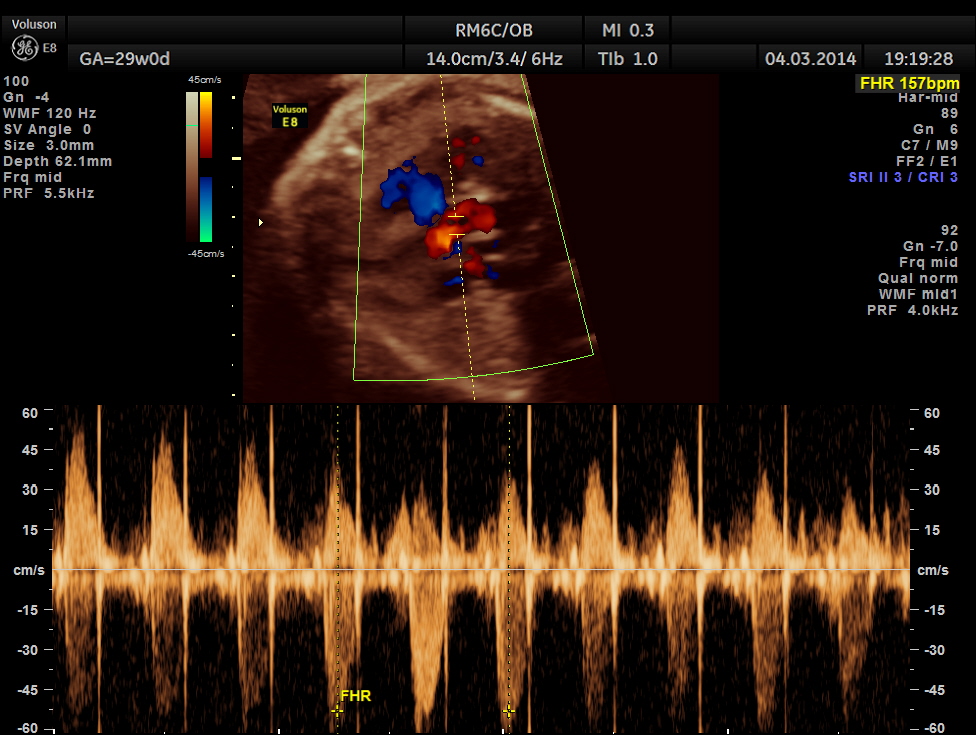

Images of the other organs are given below.